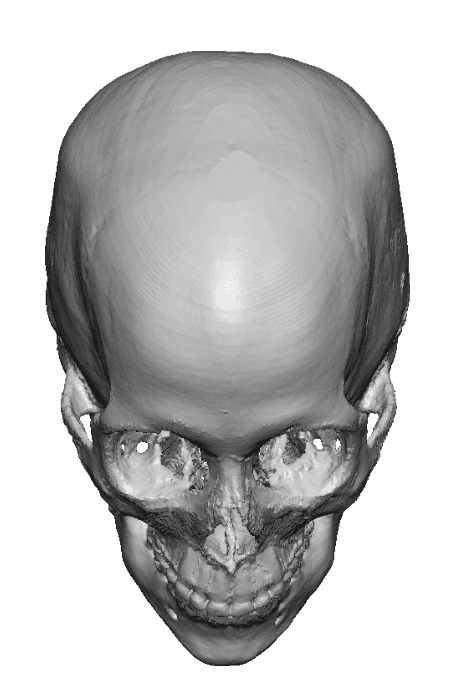

Severe narrowing skull deformity from prior sagittal craniosynostosis repair as an adult.

Complete replacement of entire skull by a custom implant with temporal fat injections.

Severe narrowing skull deformity from prior sagittal craniosynostosis repair as an adult.

Complete replacement of entire skull by a custom implant with temporal fat injections.